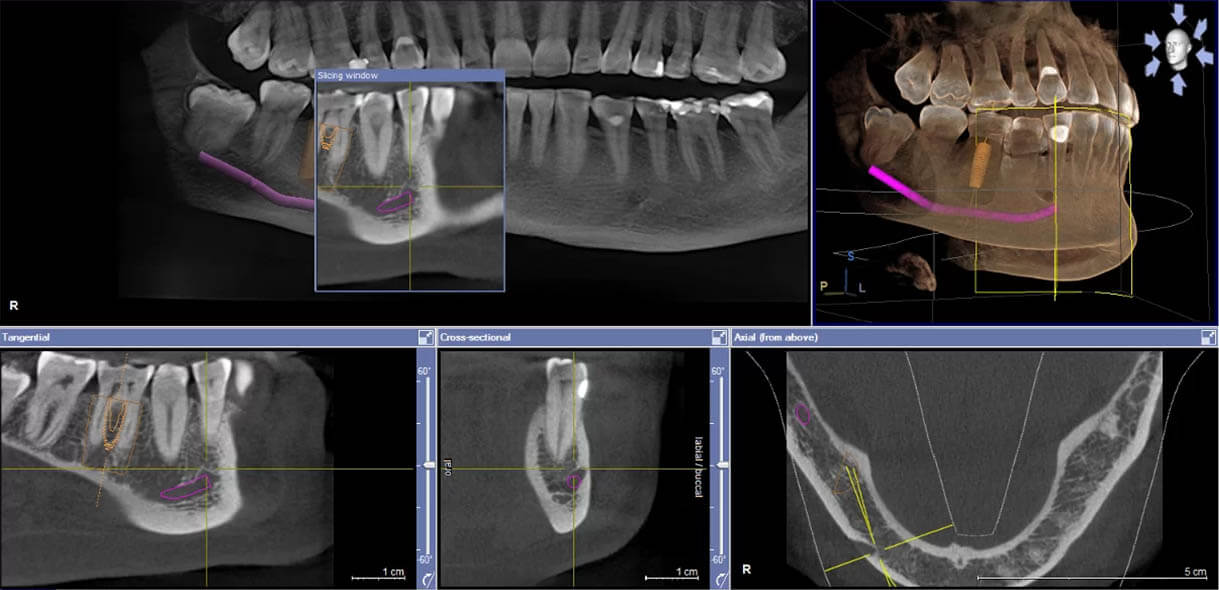

A 3D X-ray scan is painless, takes just a moment, and requires no preparation. Thanks to it, the dentist can comprehensively assess the condition and structure of your teeth. Even the most thorough dental examination isn’t always enough to properly diagnose a patient. That’s why dentists are increasingly using modern technologies, such as 3D radiography. With 3D imaging, the doctor gains complete information about the teeth from every angle. They can even see inside the teeth and bones, which gives them a full picture of the patient’s condition. As a result, the dentist can identify issues that are impossible to see during a “standard” check-up. At the same time, 3D images help dentists clearly explain the situation to patients in an accessible way.

Not every patient’s problem can be diagnosed during a “standard” dental examination. Some conditions can only be seen with modern equipment, such as an X-ray machine. 3D X-ray allows dentists to reach a higher level of diagnostics. 3D imaging is particularly important for diagnosing periodontal and pulp diseases, as well as inflammations. Thanks to it, making the right diagnosis and finding the most effective treatment becomes much easier!

3D image taken with CBCT technology (tomography):